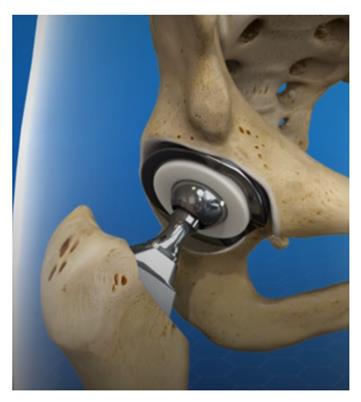

A robotic system designed to assist surgeons in performing minimally invasive hip replacement surgery with improved precision and reduced costs.

This project focuses on developing an innovative, cost-effective robotic system to assist surgeons in performing minimally invasive hip replacement surgery. The system aims to develop a low-cost minimally invasive robot system to assist with THR surgery that can automatically plan and prepare for the accurate placement of the components.

This project focuses on developing an innovative, cost-effective robotic system to help surgeons in performing minimally invasive hip replacement surgery. The system aims to assist with surgery that can automatically plan and prepare for the accurate placement of the components.